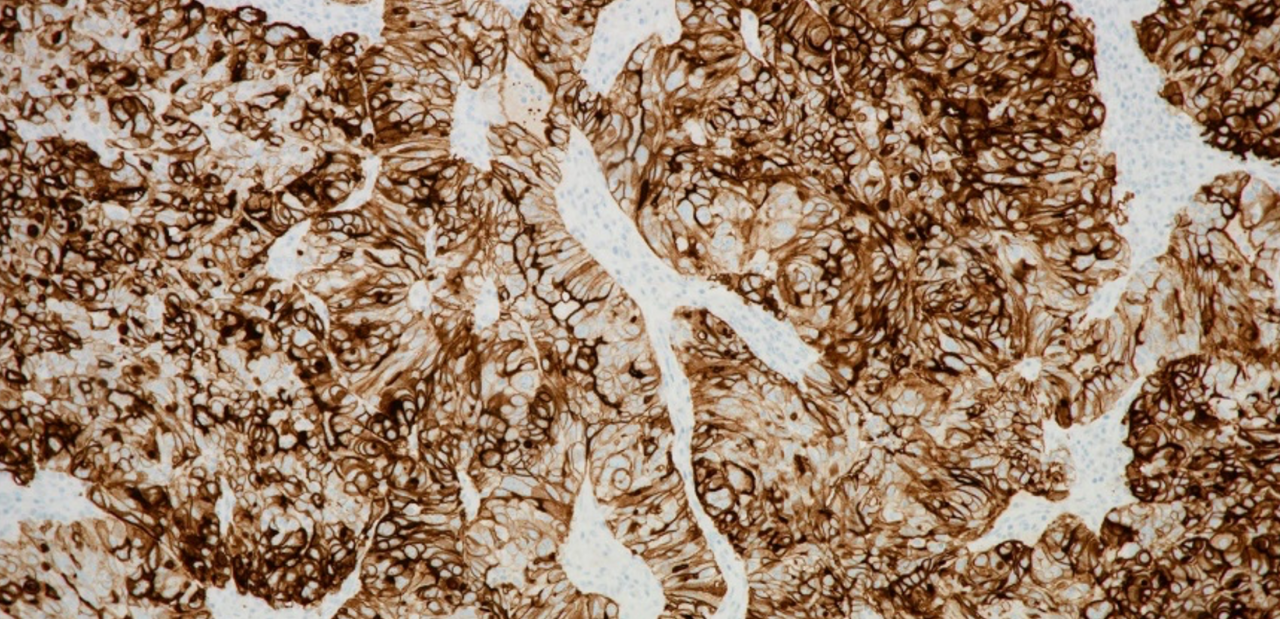

精準(zhǔn)醫(yī)療、診斷先行。精準(zhǔn)的伴隨診斷是實(shí)現(xiàn)腫瘤患者個(gè)體化精準(zhǔn)診療的先決條件,堪稱靶向治療最理想的“助攻”。此次獲批的羅氏診斷VENTANA FOLR1抗體檢測試劑,可通過染色強(qiáng)度水平為2+和3+的膜染色的腫瘤細(xì)胞百分比(% TC)確定FOLR1表達(dá),輔助臨床醫(yī)生精確識(shí)別出適合接受索米妥昔單抗治療的上皮性卵巢癌、輸卵管癌或原發(fā)性腹膜癌患者。該檢測可在羅氏診斷BenchMark 全自動(dòng)免疫組化染色系統(tǒng)上實(shí)現(xiàn)全自動(dòng)化運(yùn)行,其經(jīng)過規(guī)范化、標(biāo)準(zhǔn)化的臨床驗(yàn)證,具有穩(wěn)定性高、易判讀等優(yōu)勢,可直接指導(dǎo)臨床用藥。